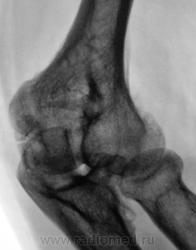

Пациент направлен на рентгенографию локтевого сустава. Была травма или не была не помнит. Пациент весьма пьющий, направлен хирургом с диагнозом "перелом". Рука в локтевом суставе полность не разгибается.

Ваше мнение уважаемые коллеги?

Наверно, застарелый перелом в области блока плечевой кости. Не понятен периостит.